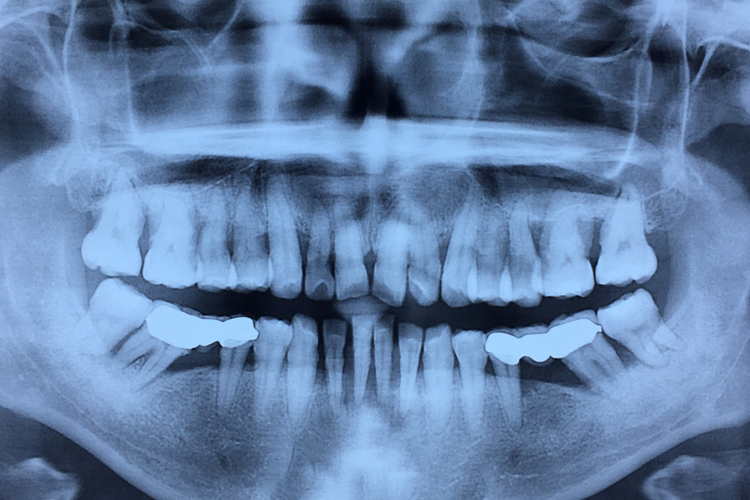

牙槽骨是上下颌骨包围和支持牙根的突起部分,骨质较疏松,且富于弹性,是支持牙的重要组织。容纳牙根的窝称牙槽窝,在冠方的牙槽窝的游离端称牙槽嵴。牙槽嵴的形态在前牙区为圆柱状,磨牙区为扁平状,而在颊舌侧变薄甚至消失。牙槽骨从X线片中,可以观察到邻间牙槽骨的高度和外形。

牙槽骨是高度可塑性组织,也是全身骨骼中变化最活跃的部分,它的变化与牙的发育和萌出、乳牙替换、恒牙移动和咀嚼功能等均有关系。生理状态下,牙咬合面及邻接面的磨耗而不断发生生理性的移位,牙槽骨也随之产生吸收和增生的改变。牙槽骨的高度可塑性,是临床上进行错(牙合)畸形矫治的生物学基础。